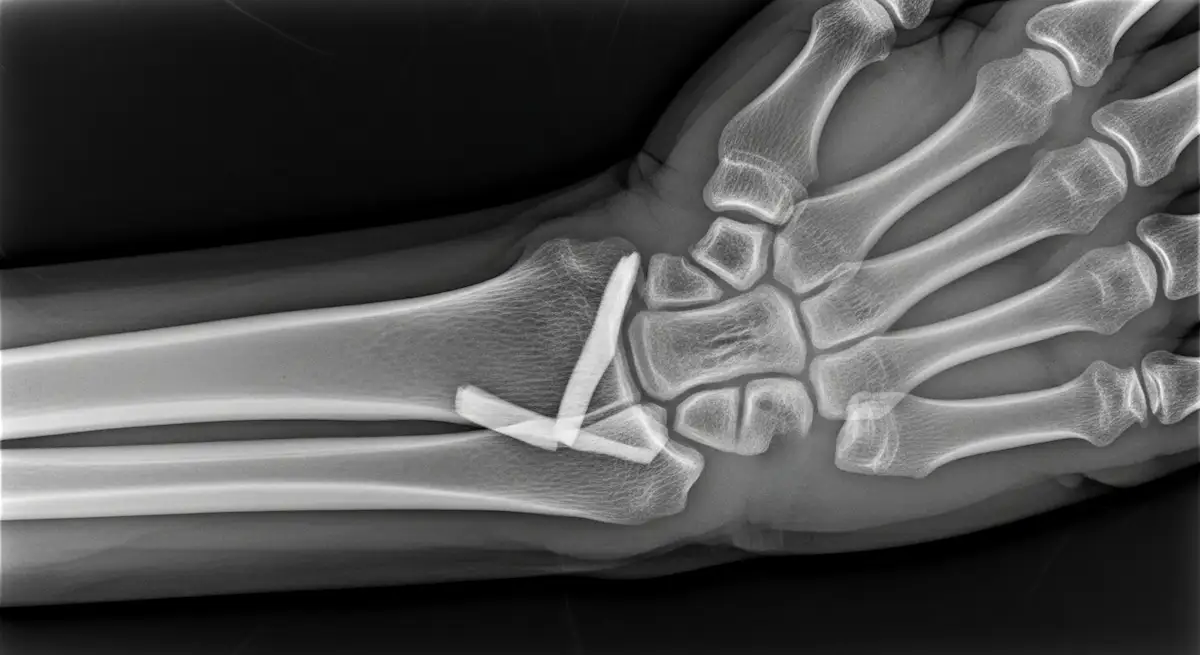

Como ortopedista especializado em cirurgia de mão em Goiânia, tenho a oportunidade de tratar uma variedade de lesões, mas as fraturas do rádio são particularmente comuns e um tanto desafiadoras. Localizadas na região distal do osso, essas fraturas afetam a…